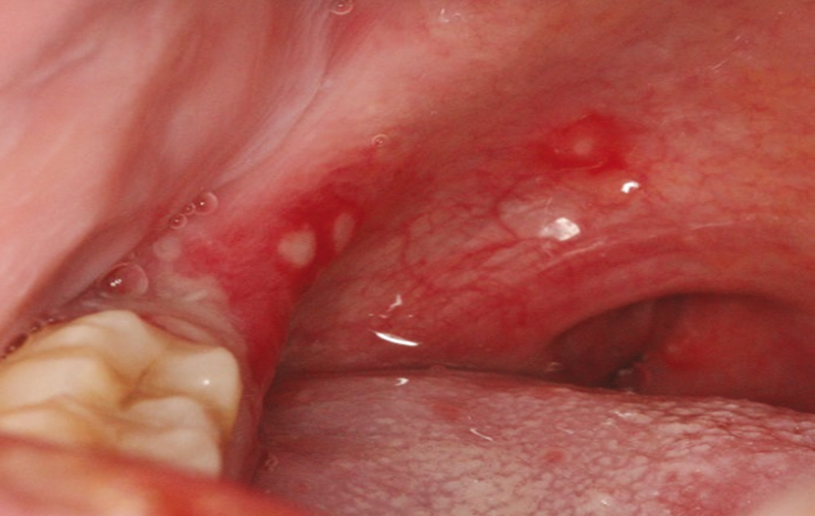

- ოროფარინგეალური არე – სტომატოლოგიური პრობლემები, ფარინგიტი, ჰერპანგინა (სურათი 1ა), HSV გინგივოსტომატიტი (სურათი 2A-B)

სურათი 1ა.

სურათი 2A-B. ჰერპესული სტომატიტი.

სამ პაციენტთან გამოხატულია პირის ღრუს ინფექციის სპექტრი რომელიც განვითარდა ჰერპეს სიმპლექსის ვირუსით, დაავადების სიმპტომატიკა მერყეობს უსიმპტომოდან მძიმე მდგომაროებამდე.

(ა) პირველ პაციენტს აქვს ერთი ვეზიკულა ენაზე.

(ბ) მეორე პავციენტთან ვლინდება ლაბიალურ დაზიანებებს.

(C) მესამე პაციენტთან გამოხატულია სახეზე გავრცელება. მცირეწლოვან ბავშვში სახის დაზიანებით, ფლუორესცეინის საღებავი ჩაწვეთთდა მარცხენა თვალში, რათა გამოვლინდეს ტიპიური დენდრიტული წყლული ჰერპესული კერატიტი.